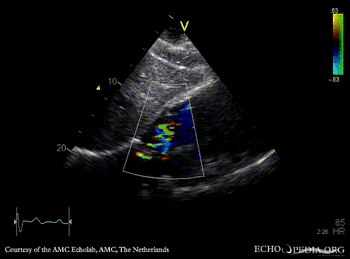

E00310.gif E00311.gif

Subcostal view: ASD type II TEE: ASD type II